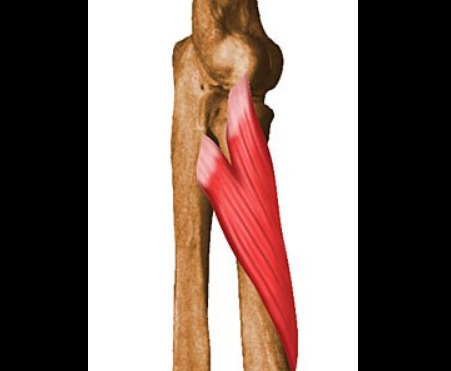

Braquial (braquial anterior)

Inserciones, inervación y función del braquial.

Origen: cara anterior del húmero, mitad distal (debajo de la deltoidea)

Inserción: tuberosidad de la ulna

Inervación: musculocutáneo (C5-C6) + contribución del radial (menor)

Función: flexor PURO del codo (independiente de prono-supinación)

Es el motor principal de flexión del codo, el bíceps es el famoso pero el braquial es el trabajador